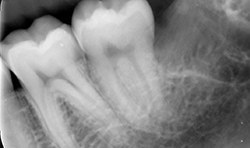

Different thin metallic blades may be connected to the Magnetic Max handpiece, sending a magnetic wave on the tip. The Magnetic Max imparted to blade a longitudinal movement along the central axis, moving up and down between root surface and lamina dura of the alveolus in a repetitive circumferential fashion, providing a driving mechanism of longitudinal movements. This movement also allows the maintenance of lamina dura for wisdom teeth (Figs. 4a-4c).

Fig. 4b

Fig. 4c